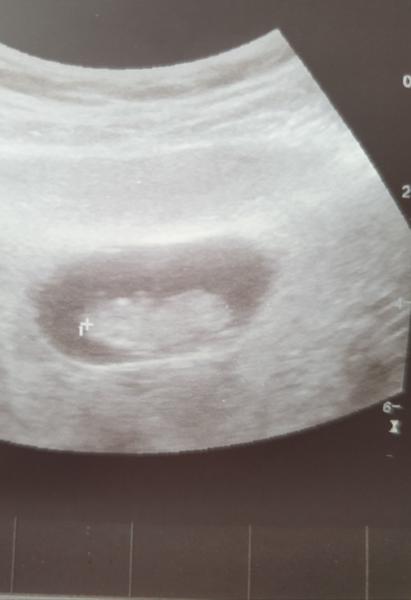

@kristynaprandl no to já jsem také zvědavá 🥰 tak na kontrole vse v poradku. Miminko je sice o 5 dní mladší,ale to vůbec nevadí. Krasne si tam kopalo a mavalo ručičkama🥰❤ ultrazvuk ma teda hroznou kvalitu,ale nevadí taky fotečka 🥰